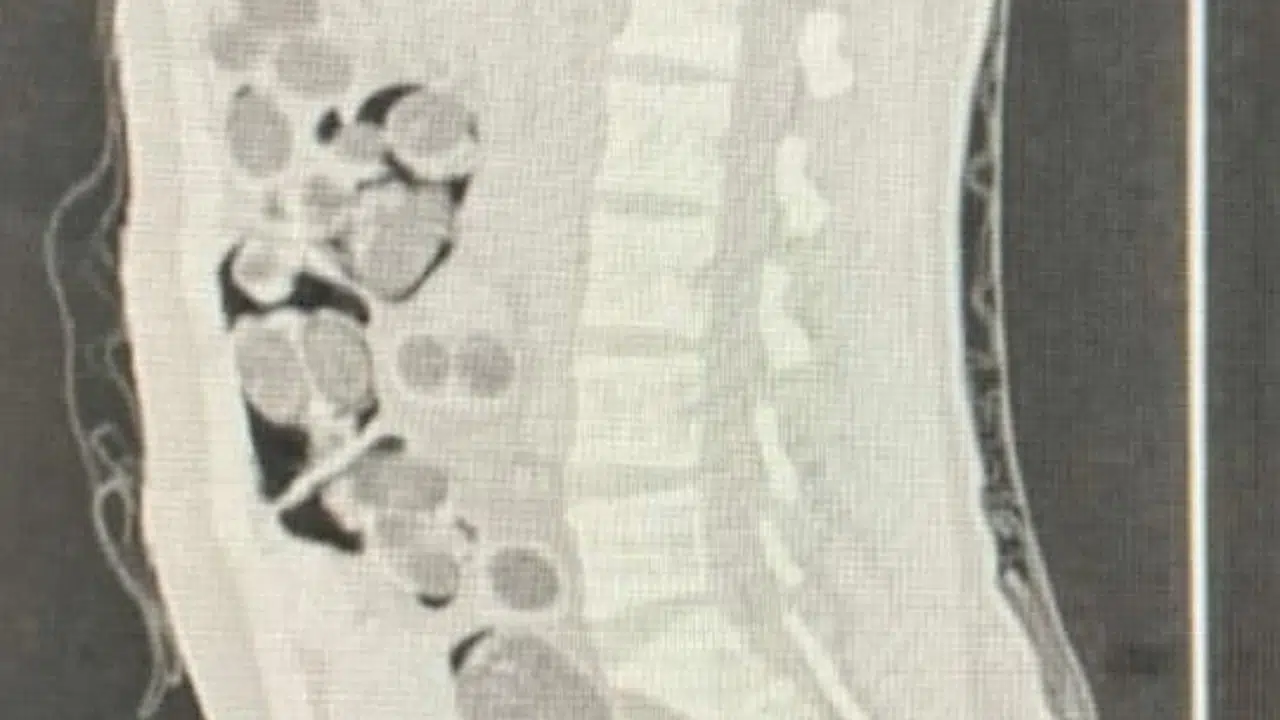

Ramazan ÇETİN/DENİZLİ, (DHA)-DENİZLİ'de uçakla seyahat eden yabancı uyruklu yolcunun midesinden 219 paket halinde 1 kilo 144 gram skunk, 178 gram metamfetamin, 90 uyuşturucu hap ve 7 gram Afyon sakızı çıktı. Şüpheli ile alıcı, operasyonla yakalanıp, tutuklandı.

Denizli İl Emniyet Müdürlüğü Narkotik Suçlarla Mücadele Şube Müdürlüğü ekipleri, 2 Şubat'ta Çardak Havalimanı'na inen yabancı uyruklu kişinin uyuşturucu taşıdığını belirledi. Takibe alınan şüpheli, uyuşturucu maddeyi teslim edeceği yabancı uyruklu alıcı ile buluştuğu sırada operasyonla yakalandı. Şüpheli ile alıcı, gözaltına alındı. Denizli Devlet Hastanesi'ne götürülüp, röntgeni çekilen yabancı uyruklu şüphelinin midesinden 219 paket halinde 1 kilo 144 gram skunk, 178 gram metamfetamin, 90 uyuşturucu hap ve 7 gram Afyon sakızı çıktı. Paketteki uyuşturucular doğal yollarla çıkartılırken, 2 şüpheli işlemlerinin ardından tutuklandı. (DHA)